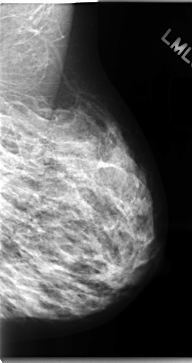

C_0098_1.LEFT_CC

LEFT_CC LINES 4680 PIXELS_PER_LINE 2504 BITS_PER_PIXEL 12 RESOLUTION 50 NON_OVERLAY